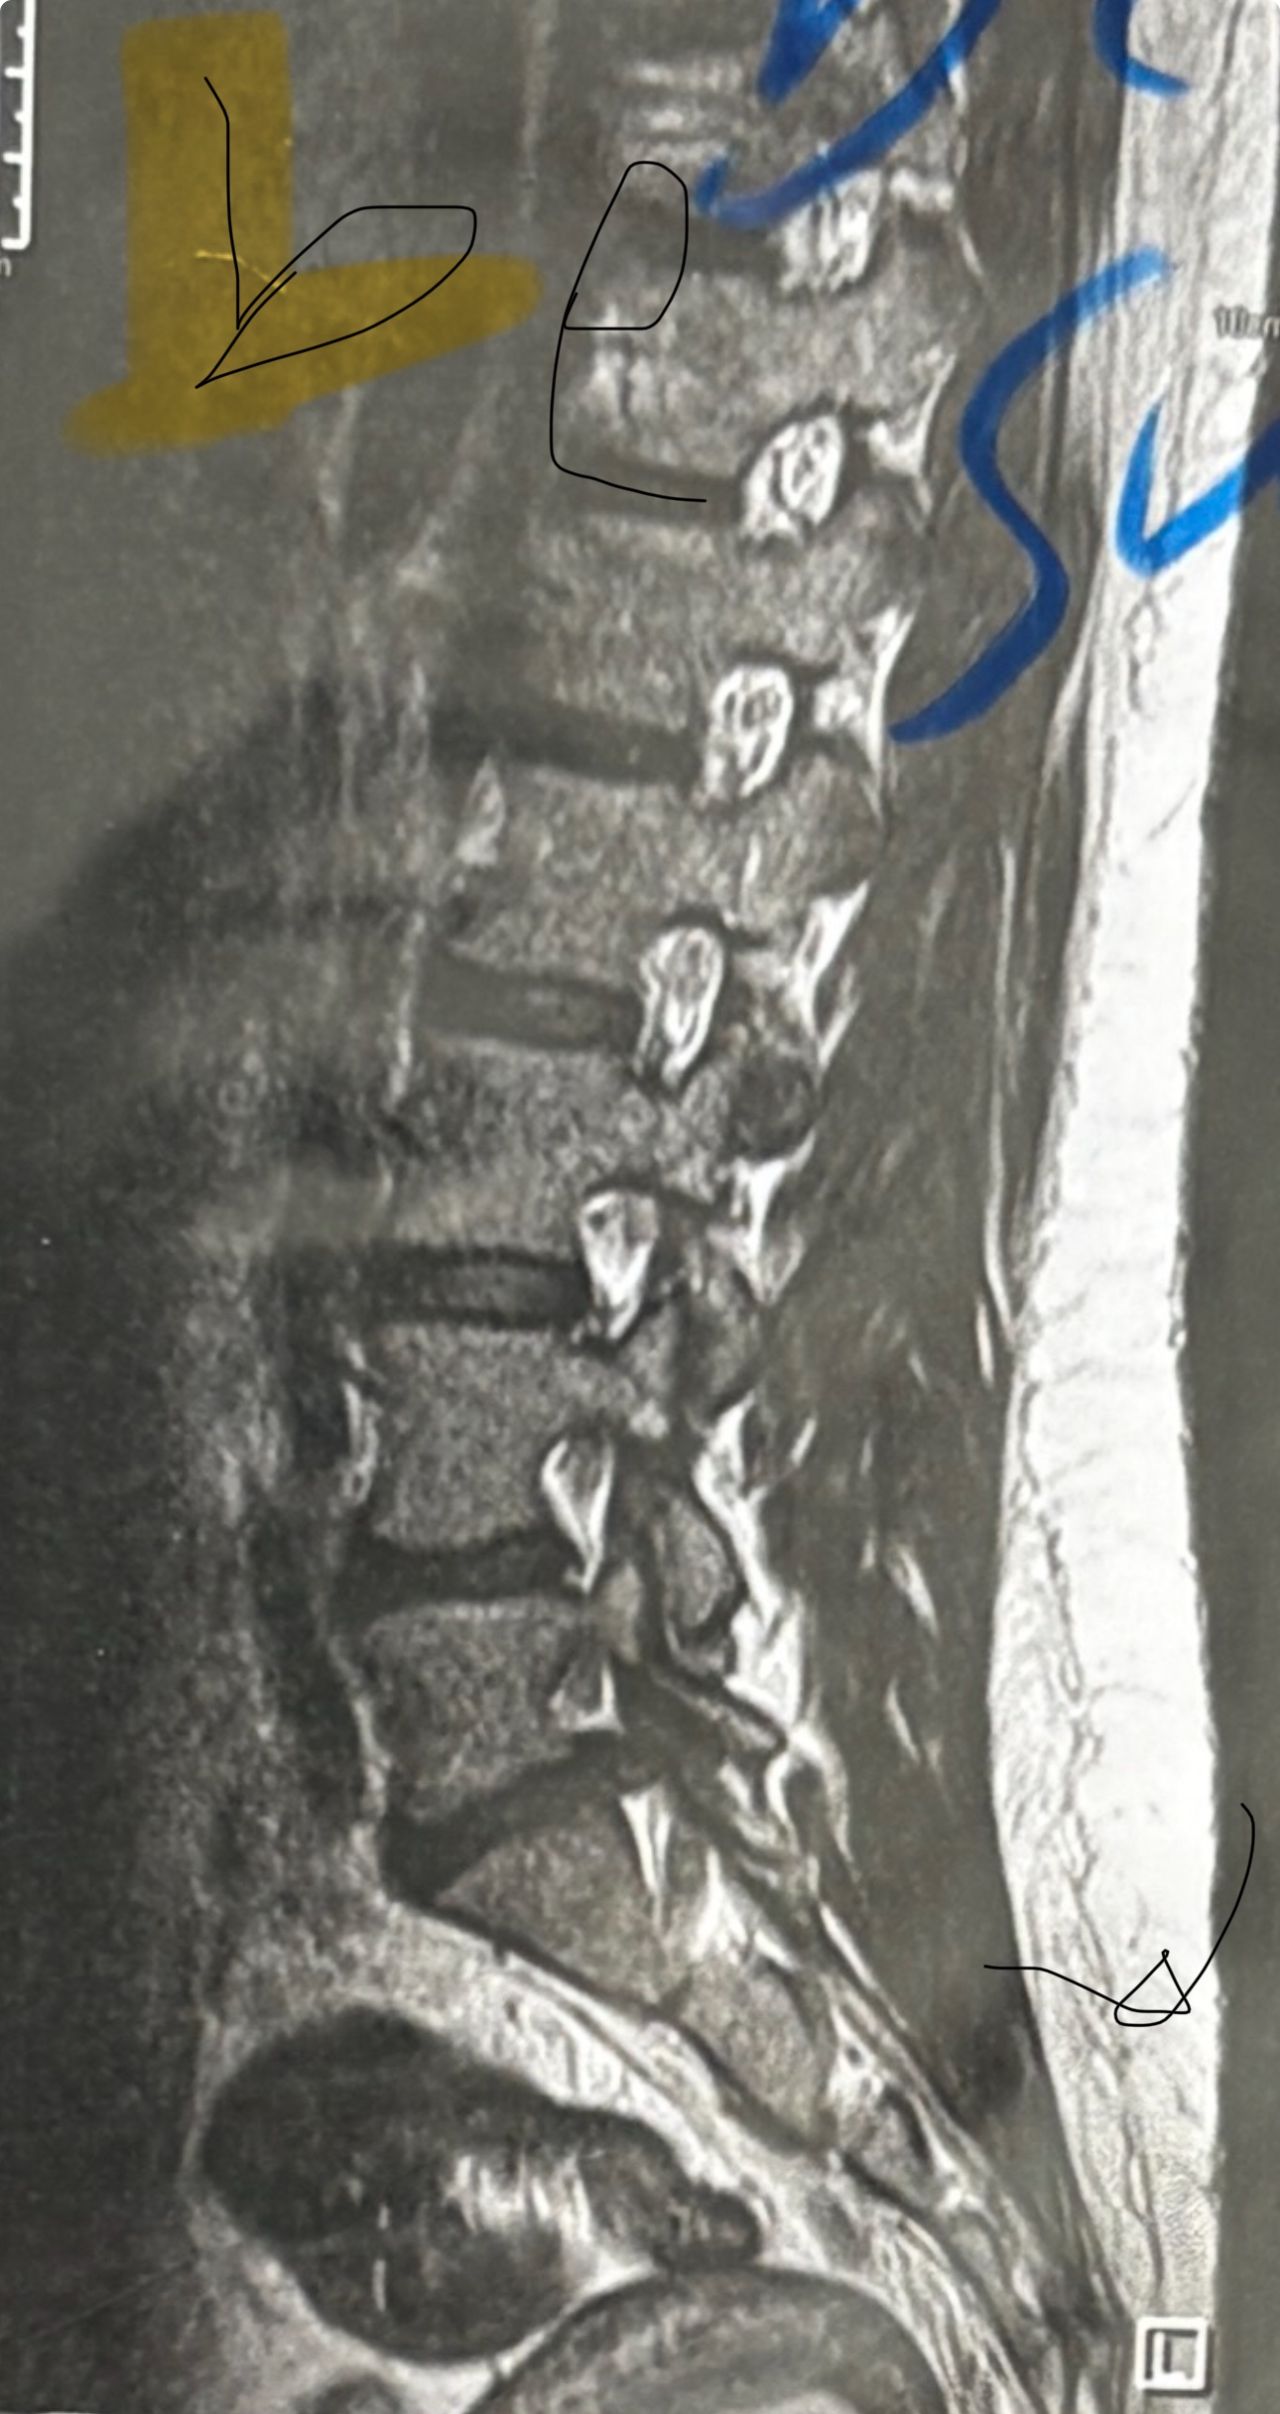

41 years old man presented to my clinic in October 2023 with acute and sever R neck pain with radicular pain to his R upper extremity along C6 dematom since 2 weeks ago. Examination didn’t show any upper motor signs. Was suggested urgent surgery

I ordered EMG/ NCV : showed mild R C6, C7 irritation without any active axonal loss

In his MRI was reported R. para R. IVF Massive extrusion. I decided to control his pain and manage this patient with reevaluation of patient every other session. For 5 sessions i just used acupuncture and laser and IFC and mild adjustments to his R. T3-T7 and mild arthosteem to above and below involved segment. Cervical adjustment considered contraindicated for this patient. From session 6th- 8th i started to use mild/gentle cervical decompression. He used soft cervical collar all the time. His pain decreased by 80 percent

I gave him cervical traction pump to be used 3-5 times per day at home for the next 3 months and i released the patient. He was evaluated every week once for one month and after that every 2 weeks. After 3 month I repeated MRI. Size of the herniated disc was reduced greater than 50 percent. Asked him to do another mri in 6 months

In general: Precise selection of the patients, examination,diagnosis, plan of management, reevaluation and treatment can be done by doctors of chiropractic for the patients with spinal disc herniation and stenosis Moreover giving reasonable time to these kind of patients under direct supervision by their chiropractic doctors can prevent unnecessary surgery. Proper selection of these kind of patients is another important fact that can be done precisely by chiropractors.

MRIs before and after proper management of this patient: